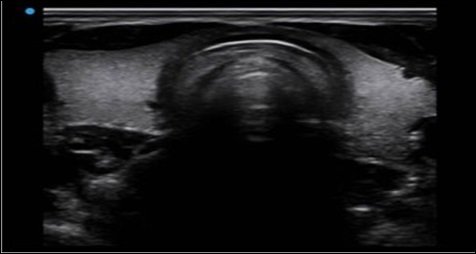

Nanopure i Nanoview

Dwa rodzaje technologii redukcji plamek są gotowe do użycia w zależności od różnych tkanek.

Nowo opracowana technologia Nanopure ma niezwykłą wydajność w skanowaniu układu

krążenia MSK i narządów powierzchownych, podczas gdy Nanoview zachowuje swoją przewagę

w optymalizacji obrazu brzucha i OB/Gin.